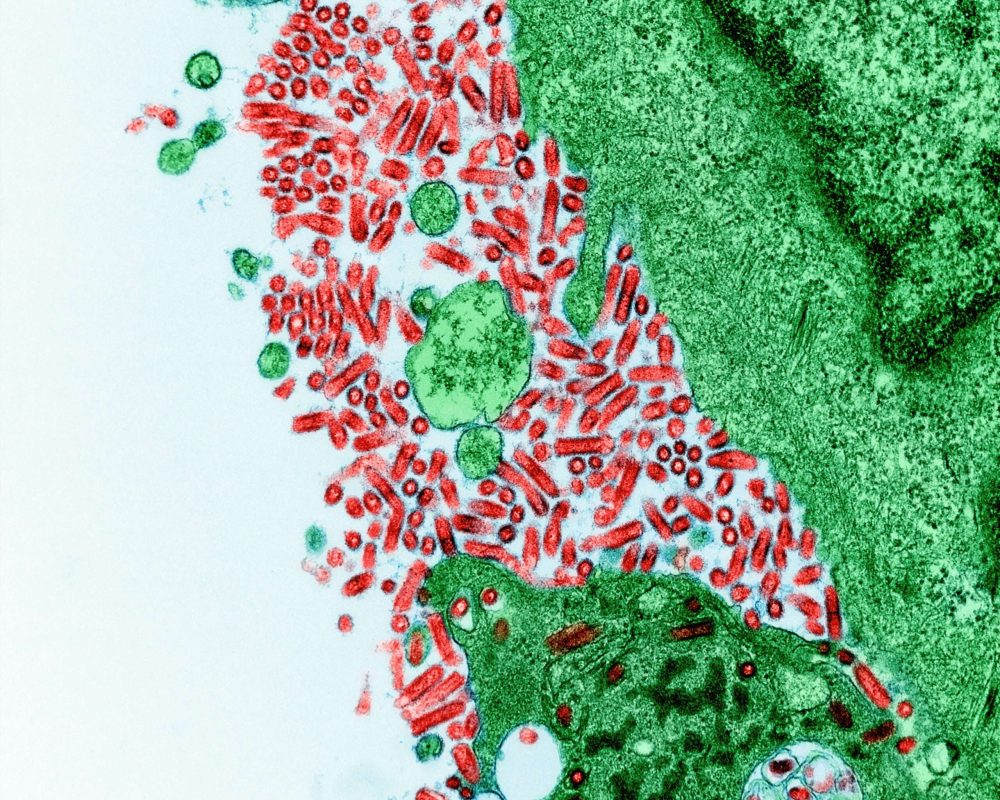

Vírusok és baktériumok

Az édes üröm (Artemisia annua) nemcsak a malária elleni küzdelemben bizonyult különlegesnek, hanem egyre több kutatás vizsgálja, hogy hatóanyaga milyen széles körű vírus- és baktériumellenes hatásokkal rendelkezhet. A hatóanyag különlegessége a molekulaszerkezetében rejlik. Amikor olyan környezetbe kerül, ahol sok vas található, például fertőzött sejtekben, szabad gyököknek nevezett reaktív molekulákat szabadíthat fel. Ezek a molekulák oxidatív stresszt idézhetnek elő, ami laboratóriumi vizsgálatok szerint károsíthatja a kórokozók fehérjéit és védőburkát. Ez magyarázza, hogy a hatást vizsgálatokban elsősorban a fertőzött sejtekben figyelték meg, míg az egészségeseket kevésbé érintette. Vírusok esetében több laboratóriumi kutatás is azt mutatta, hogy a növényből kivont hatóanyag és származékai megzavarhatják a vírusok szaporodását. A vírusfertőzések során a kórokozó átveszi az irányítást a sejtek felett, és saját másolatait gyártatja le velük. Vizsgálatokban a hatóanyag képes volt beavatkozni ebbe a folyamatba, így csökkentve a vírus másolódását. Ígéretes eredmények születtek például a hepatitisz-vírusokkal kapcsolatban (ahol a májsejtek védelmét figyelték meg), az influenza-vírusoknál (ahol mérséklődött a vírus replikációja), valamint a koronavírusok esetében is folytak vizsgálatok. Baktériumok esetében a növény hatása szintén figyelemre méltó. Vizsgálatok szerint gátolhatja olyan kórokozók növekedését, mint a Staphylococcus aureus, a Streptococcus pneumoniae vagy az Escherichia coli. Az egyik különlegessége, hogy képes lehet akadályozni a baktériumok biofilm-képződését. A biofilm egy védekező réteg, amelyet a baktériumok hoznak létre, és ami miatt sokszor ellenállnak az antibiotikumoknak. Ha a hatóanyag ezt a védelmet gyengíti, a kórokozók sérülékenyebbé válhatnak. Emiatt egyre inkább vizsgálják antibiotikumokkal kombinálva, ahol kiegészítő szerepe lehet a kezelések hatékonyságának növelésében. A növényből kivont hatóanyag hatásai nem korlátozódnak a kórokozókra. Számos kutatás szerint képes lehet az immunrendszer működésének támogatására is. Egyrészt mérsékelheti a túlzott gyulladásos reakciót, másrészt fokozhatja a szervezet védekezőképességét a fertőzésekkel szemben. Ez a kettős hatás abban nyilvánulhat meg, hogy egyszerre hathat közvetlenül a kórokozókra, és egyidejűleg támogathatja az immunrendszert is.